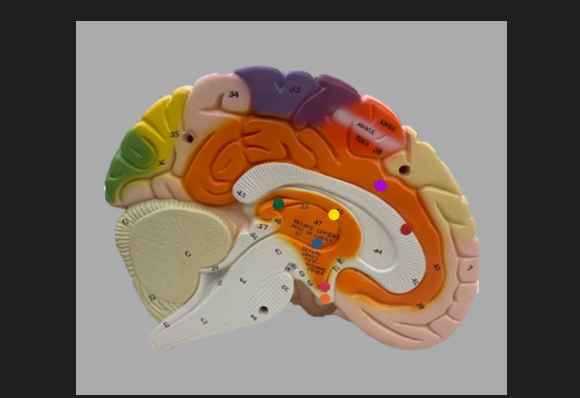

orange dot

frontal lobe

blue dot

longitudinal fissure

dark green dot

precentral gyrus

pink dot

postcentral gyrus

yellow dot

central sulcus

white dot

parietal lobe

light green dot

Broca’s Area

red dot

Wernicke’s Area

orange dot

occipital lobe

blue dot

parieto-occipital sulcus

blue dot

olfactory tract

red dot

corpora quadrigemina

dark green dot

cerebral aqueduct

blue dot

cerebral penduncles

pink dot

pons

orange dot

medulla oblongata

yellow dot

mammillary body

red dot

corpus callosum

dark green dot

pineal gland

yellow dot

epithalamus

blue dot

thalamus

orange dot

optic chiasm

pink dot

infundibulum

purple dot

cingulate gyrus

yellow dot

pituitary gland

dark green dot

pyramids

red dot

olives

blue dot

optic tract

purple dot

midbrain

green dot

folia

orange dot

arbor vitae

yellow dot

fourth ventricle

red dot

vermis

blue dot

hypothalamus

pink dot

cerebral hemispheres

yellow dot

lateral sulcus

red dot

lateral ventricles

blue dot

hippocampal gyrus

green dot

olfactory tract